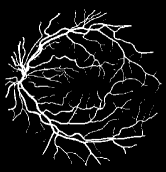

As pointed out in recent works [15, 17], a good semantic segmentation network should learn multi-level features. Further, it should have multiple stages with different receptive fields to learn more inherent features from different scales. FCN, taken as an example, uses skip connections to fuse multiple stages outputs, as well as the HED network, in which a series of side-output layers are added after each stage in VGGNet. The HED network was first proposed for edge detection, and further used for image-level vessel segmentation in recent studies [6, 16], with significant performance. However, our experimental results show that such network architecture is not appropriate for vessel segmentation directly. Figure 1 provides such an illustration. Reasons for this phenomenon are straightforward. On one hand, the side-output of the first layer often contains too many noises. On the other hand, the features produced by the last side-output layer are too coarse due to information loss of pooling operation. Obviously, the inaccurate vessel map of side-output1 and side-output4 should have negative impacts on the final segmentation result.

With the deepening of DSN network, the receptive field of each side-output layer gets larger, which makes the corresponding vessel map much blurrier as observed from the first row in Figure 1, especially for side-output4. These observations inspired us to pass low level fine semantic information to high levels to alleviate the blurring situation.

Bottom-top short connections aim to refine high-level segmentation results. However, we can observe from the first two rows in Figure 1 that the vessel map generated by the first side-output layer contains too many noises while the map generated by the last side-output could capture the main vessel structure. Therefore, we propose delivering high-level structural information to the first side-output layer to reduce its noises. We implemented this kind of information delivery by a top-bottom short connection from conv4 to feat_conv1, which can been seen in Figure 4. We first convolved the last convolution of conv4 using 1 convolution kernels with size 33. Then the obtained feature map are up-sampled 8 to get feat_4_1. The information (feat_4_1) passed from conv4 are concatenated with feat_conv1 to form feat_conv1_fuse (see Figure 5). At last, one hand hand, we perform a 11 convolution operation on feat_conv1_fuse to get the information (feat_1_2) delivered to feat_conv2. On the other hand, we performed convolution operation with a kernel size of 11 and sigmoid transformation for feat_conv1_fuse sequentially to obtain the segmentation result (side 1). At last, side 1 is compared with the ground truth to get the loss of the first side-output layer.

In addition, we can observe from Figure 1 that the side-output1 and side-output4 of the BTS-DSN were more accurate compared with those of the DSN.

The segmentation results of image-level input BTS-DSN on three datasets are shown in Figure 6. We can observe from Figure 6 that the binary vessel segmentation results of BTS-DSN can recognize very coarse vessels. However, for thin vessels, the segmentation results are intermittent and many thin vessels cannot be identified.